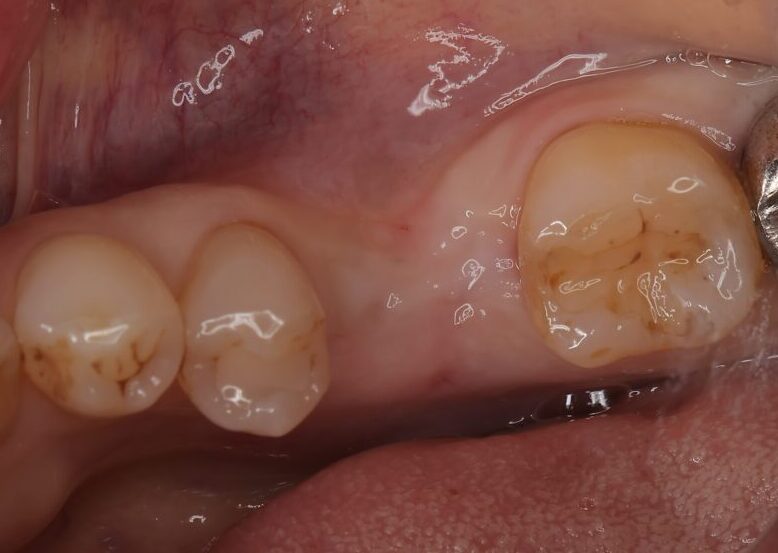

治療前の状態|左下の奥歯が欠損し、食事がしづらい状態でした

初診時の写真

左下の奥歯が欠損しており、奥歯でしっかり噛みにくい状態でした。

奥歯を失ったまま時間が経つと、隣の歯が傾いたり、噛み合う歯が伸びてきたりすることがあり、噛み合わせ全体に影響する場合があります。

▲ 治療前:左下奥歯の欠損部の状態